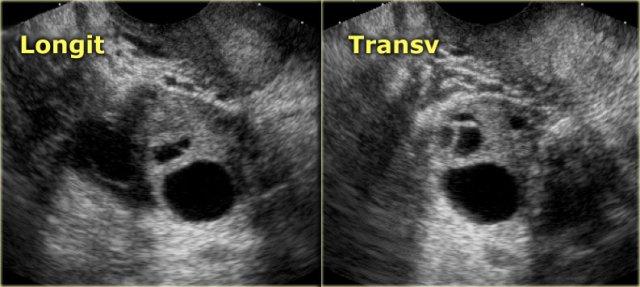

Buồng trứng bình thường ở phụ nữ tiền mãn kinh chứa các nang nhỏ.

Các hình ảnh cho thấy hai buồng trứng bình thường với nhiều nang đơn giản, không có âm vang, phù hợp với các nang Graaf.

Bẫy chẩn đoán trên FDG-PET – buồng trứng bình thường ở phụ nữ tiền mãn kinh

Ở một số phụ nữ tiền mãn kinh, buồng trứng bình thường có thể bắt FDG mạnh trên PET, tùy thuộc vào thời điểm trong chu kỳ kinh nguyệt.

Do ở phụ nữ tiền mãn kinh, buồng trứng dương tính trên PET có thể là u phần phụ hoặc hoàn toàn bình thường, điều quan trọng là phải nhận thức được khả năng bắt FDG sinh lý vào giữa chu kỳ và cần đối chiếu với bệnh sử lâm sàng.

Do đó, FDG-PET ở phụ nữ tiền mãn kinh nên được lên lịch ưu tiên vào tuần đầu tiên của chu kỳ kinh nguyệt.

Ở phụ nữ hậu mãn kinh, buồng trứng bình thường chỉ bắt FDG tối thiểu.

Bất kỳ sự tăng bắt FDG tại buồng trứng nào ở nhóm tuổi này đều gợi ý khả năng có u tân sinh.